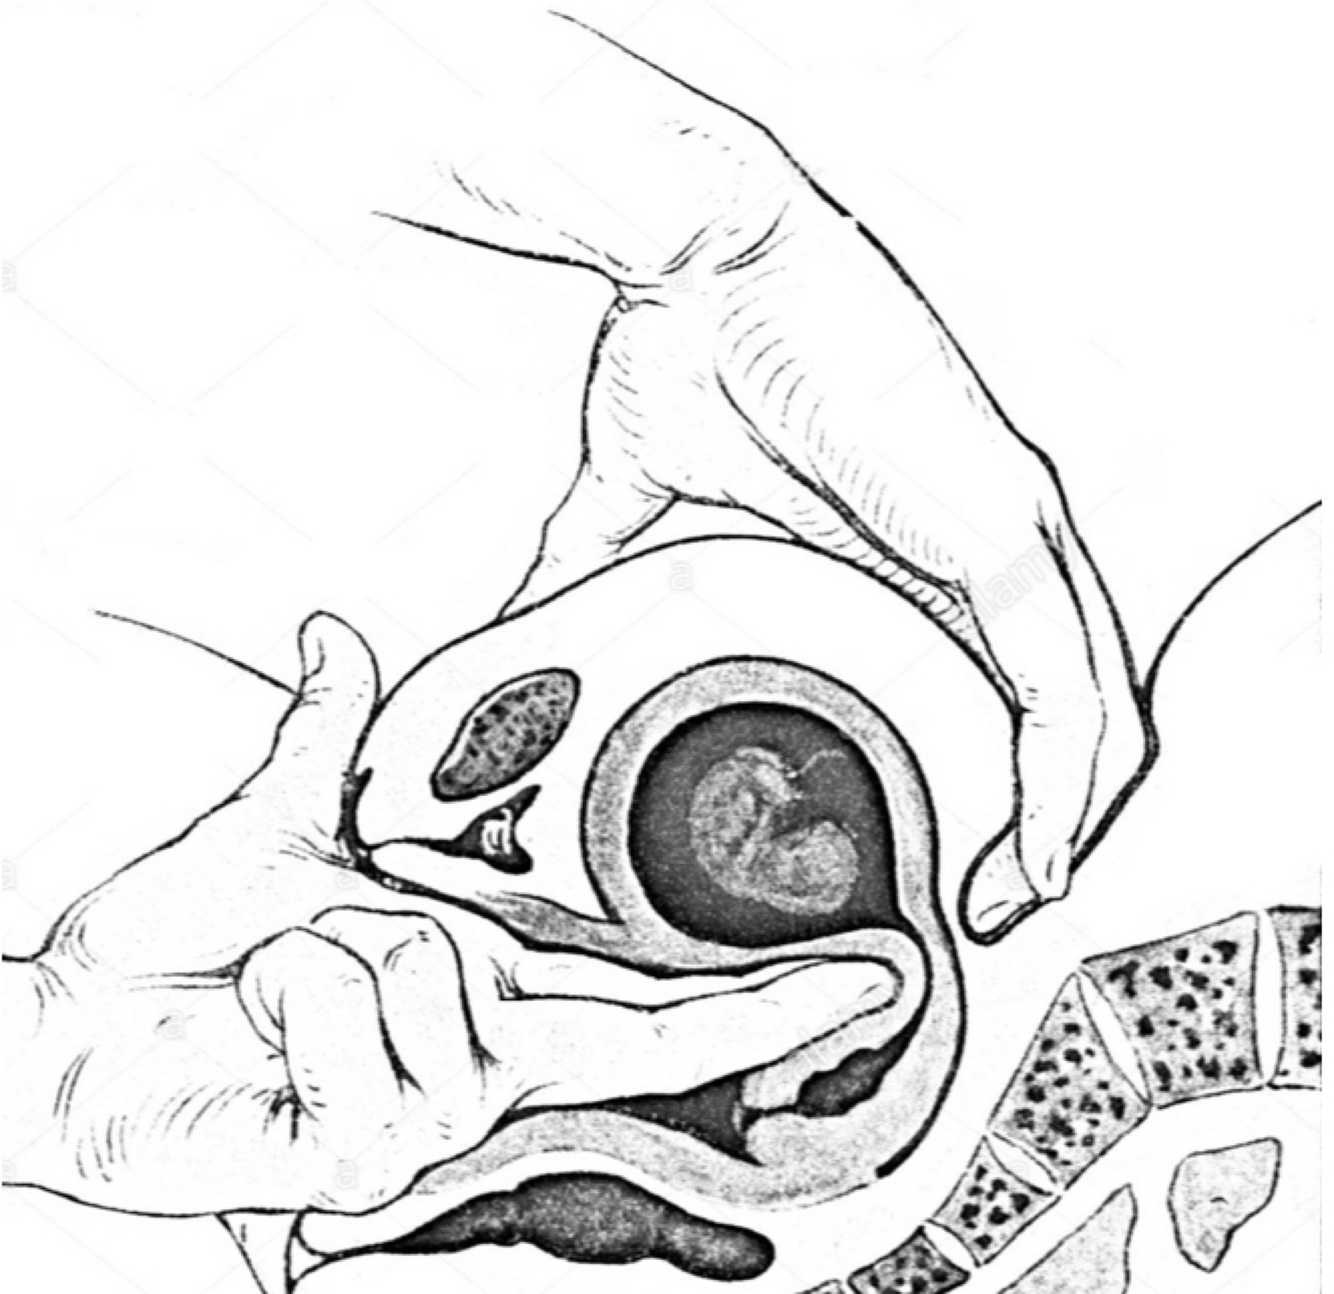

Os principais objetivos da ultrassonografia no primeiro trimestre gestacional incluem avaliar a localização da gestação e confirmar a viabilidade fetal.

Verdadeiro: A ultrassonografia no primeiro trimestre tem esses objetivos.